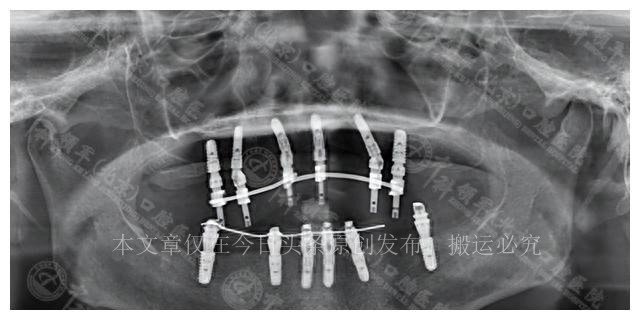

它涉及拔掉上下两颗牙齿,然后种植12颗种植体。虽然这个方案费用较高,达到7万元,但只需要3次复诊,相对来说更为便捷。

在母女之间的激烈讨论中,李女士坚定地选择了即拔即种的全口种植方案。她考虑到自己的年龄和身体状况,不愿意经历漫长的治疗过程,更不愿意将来反复赴医院。尽管费用较高,但她认为这个决定值得。在手术后,李女士的康复进展顺利,她不再感到吃饭是一种负担,身体也慢慢恢复了活力,她重新找回了生活的乐趣。